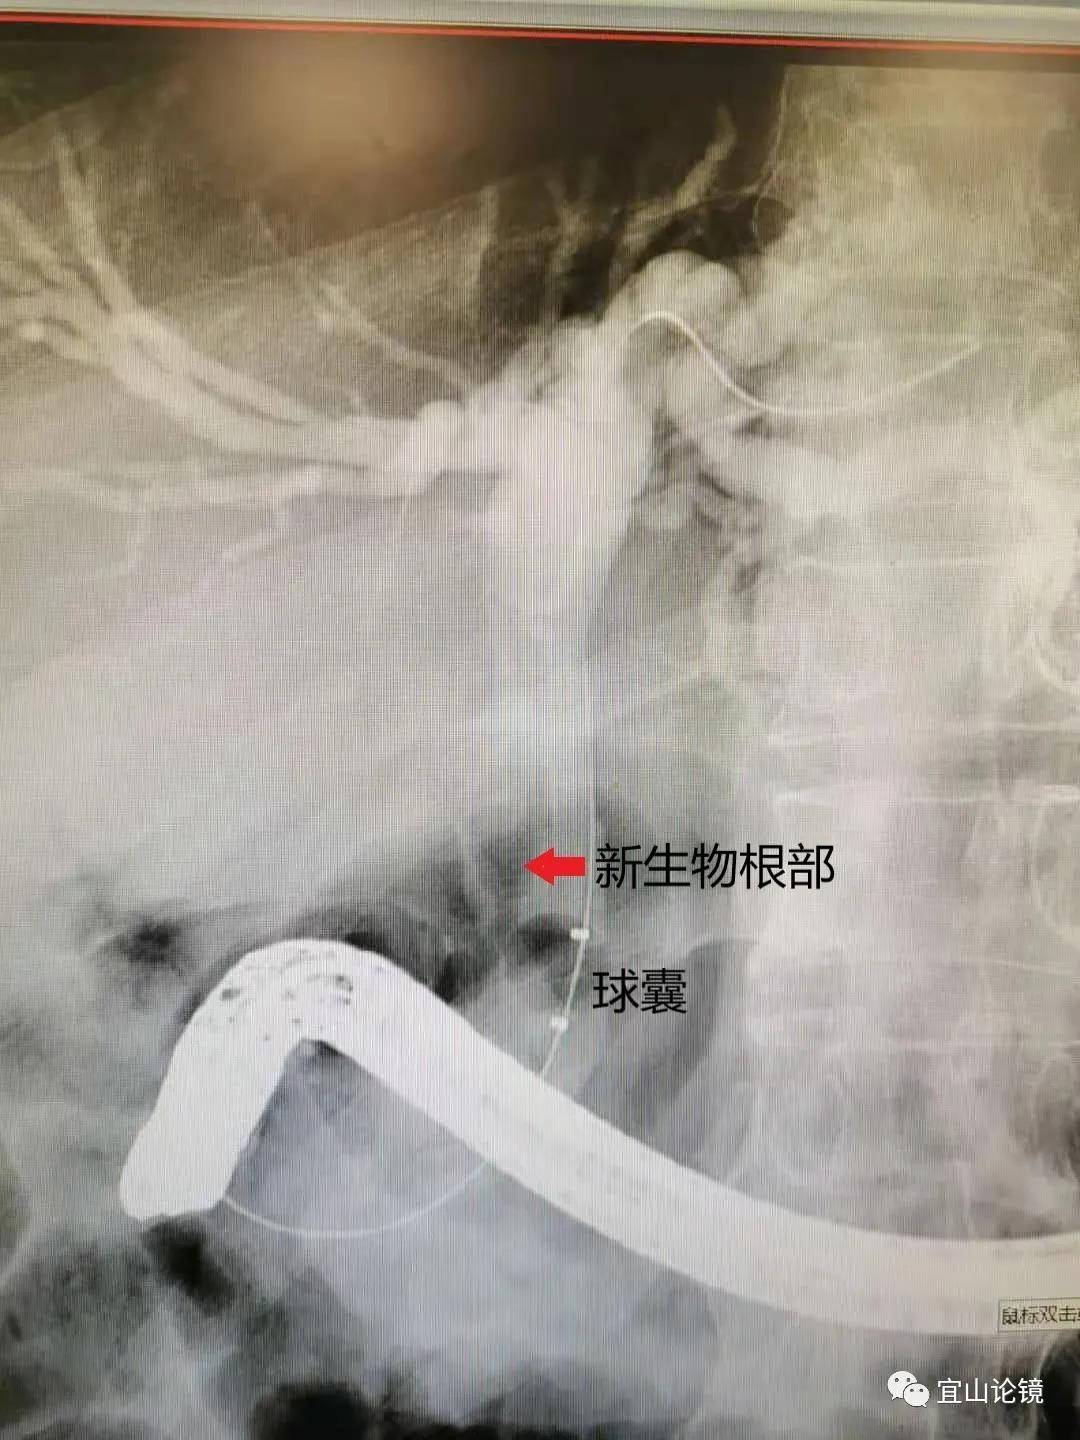

心中疑问产生:难道是胆管壁黏膜层新生物?于是请宛主任来现场指导工作,有了后续操作。首先长镜身显露胆管全程,胆管注入适量造影剂,球囊维持小于管腔直径锁定,在充盈缺损的上下拖动球囊,以看清缺损是否能被移动及大小是否改变,如下图所示。这枚“结石”能变化大小,能动,但不能被推到胆管上段,应该是一枚“胆管息肉”。于是刷检、活检,放置鼻胆管。